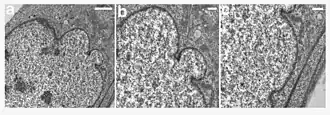

Ultrastructural analysis of the nuclear envelope in fibroblasts from a subject with HGPS. Low magnification transmission electron microscopic image of a passage 10 PT001 nucleus showed several herniations (a). Two higher-magnification images of the same nucleus at sites of blebs (b and c) showed a close apposition of the chromatin to the nuclear envelope. In a, b, and c, the nucleus is to the left. Scale bars correspond to 2 μm in panel a, and 500 nm in panels b and c.